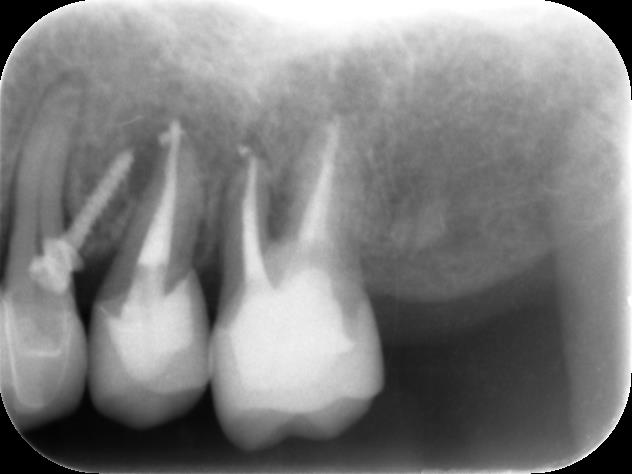

こちらが局所のレントゲン写真です

根っこの先に膿が溜まってしまい、根尖病変ができてしまっています。また、5番目は上の補綴と大きくズレてしまっているため、破折してしまっている可能性もあります。

ブリッジにぐらつきがあるのは本来2本の歯で支えていた上の補綴がほぼ6番目だけの力で支えている状態になってしまっているためです。